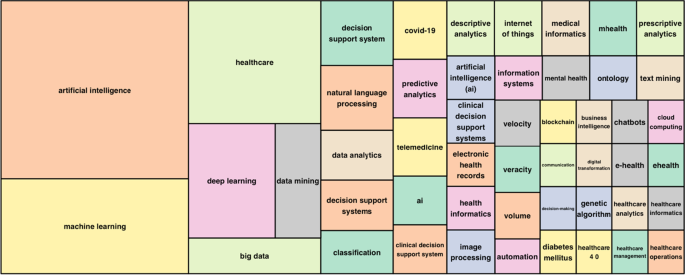

Country total articles

Figure 9 and Table 10 display the countries where AI in healthcare has been considered. The USA tops the list of countries with the maximum number of articles on the topic (215). It is followed by China (83), the UK (54), India (51), Australia (54), and Canada (32). It is immediately evident that the theme has developed on different continents, highlighting a growing interest in AI in healthcare. The figure shows that many areas, such as Russia, Eastern Europe and Africa except for Algeria, Egypt, and Morocco, have still not engaged in this scientific debate.

Country publications and collaboration map

This section discusses articles on AI in healthcare in terms of single or multiple publications in each country. It also aims to observe collaboration and networking between countries. Table 11 and Fig. 10 highlight the average citations by state and show that the UK, the USA, and Kuwait have a higher average number of citations than other countries. Italy, Spain and New Zealand have the most significant number of citations.

Articles per country.